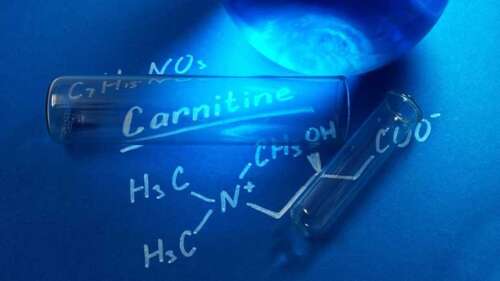

What Do L-Carnitine Supplements Really Do?

Dr. Joseph Mercola DO - Mar 6th 2024 10:33pm EST